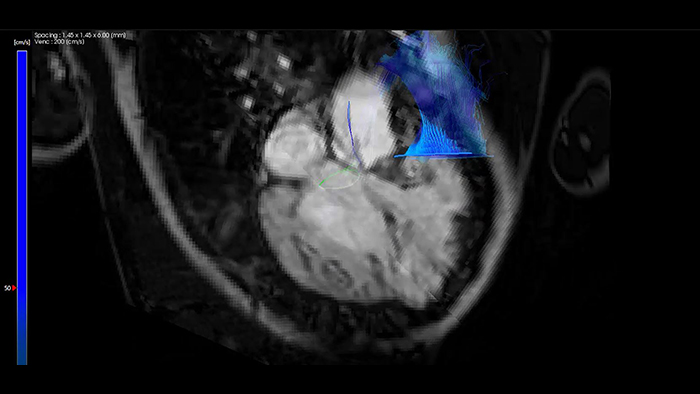

IntelliSpace Portal MR Caas 4D flow in Tetralogy of Fallot